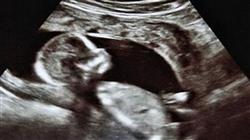

Физиология беременности и ведение родов — одна из фундаментальных отраслей акушерства и родовспоможения. С развитием медицины и технологий открываются новые факты, касающиеся развития плода и ухода за ним в процессе родов. Поэтому акушеркам необходимо обновлять свои знания в этой области, чтобы оказывать качественную помощь своим пациентам. Чтобы помочь вам в достижении ваших академических и профессиональных целей, TECH разработал Курс профессиональной подготовки в области физиологии беременности и родов для акушеров.